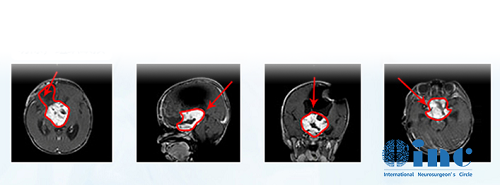

术前MR

国内一次手术后